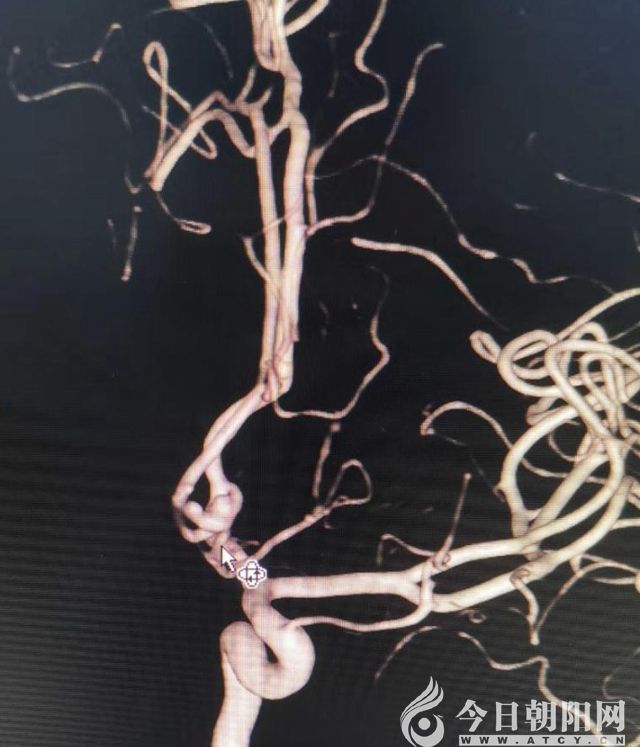

栓塞后DAS成像